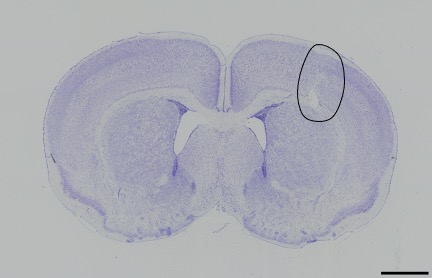

Neuroprotective Agents

Our research laboratory focuses on the evaluation of potential neuroprotective drugs in different in vivo and in vitro models to counteract newborn brain injury (Fig. 2). One current focus is on evaluation of the therapeutic potential of endogenous sigma-1 receptor ligands, such as dehydroepiandrosterone and its sulphate ester, and of levomepromazine, a phenothiazine neuroleptic drug with strong analgesic and sedative properties.